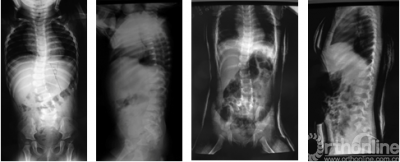

8岁男性患儿,先天性脊柱侧弯(半椎体畸形), 行半椎体切除,术前术后X线片对比

13岁男性患儿,脊柱后凸畸形(腰2半椎体),合并腰5/骶1椎体滑脱,术前术后X线片及外观对比

14岁男性患儿,休门氏病后凸畸形(重度,体重260斤),行顶椎多节段Ponte截骨术,术前术后X线片对比

14岁男性患儿,先天性脊柱侧凸骺阻滞术后11年、重度僵硬性侧后凸畸形,行顶椎区域多段脊椎截骨术,术前术后X线片及外观对比